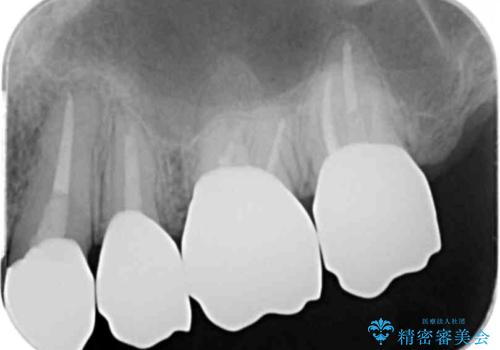

- 「虫歯が多発し、治療が終わらない。歯も無くなったし今後悪くならないような治療をしたい。」と精密治療を希望され来院されました。

虫歯の徹底的な除去やセラミック補綴、精密根管治療、歯周外科を行うことで、治療後に歯磨きがしやすく、かみやすい機能的な仕上がりへと導きます。

- 63.8万円(ジルコニアクラウン×4・仮歯×4・歯周外科) (上顎左側臼歯4本分の費用)費用は治療当時の料金となります

歯周外科手術をおこなったことでフェルールも獲得でき、破折リスクをより抑えることにも成功しています。